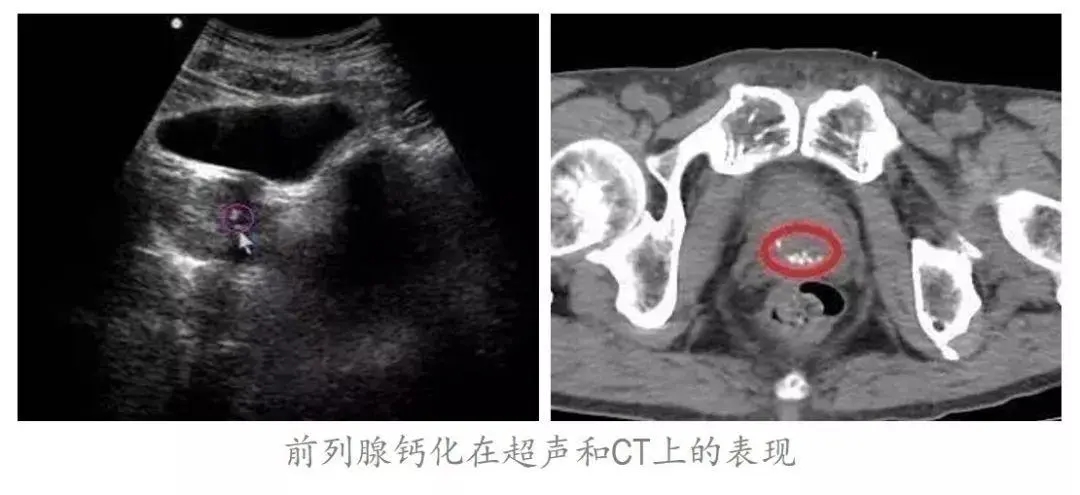

中医认为,慢性前列腺炎,其实就是虚损病,前列腺钙化(里结)所致。

▲前列腺钙化的表现

根据我们临床观察,90%的慢性前列腺炎患者,都有非常严重的前列腺增生和钙化,原因是什么呢?因为患者的身体虚弱,影响了正常的排尿功能,造成了尿无力的发生;结果本来能顺利排出来的结石,反而日积月累堵在了前列腺。